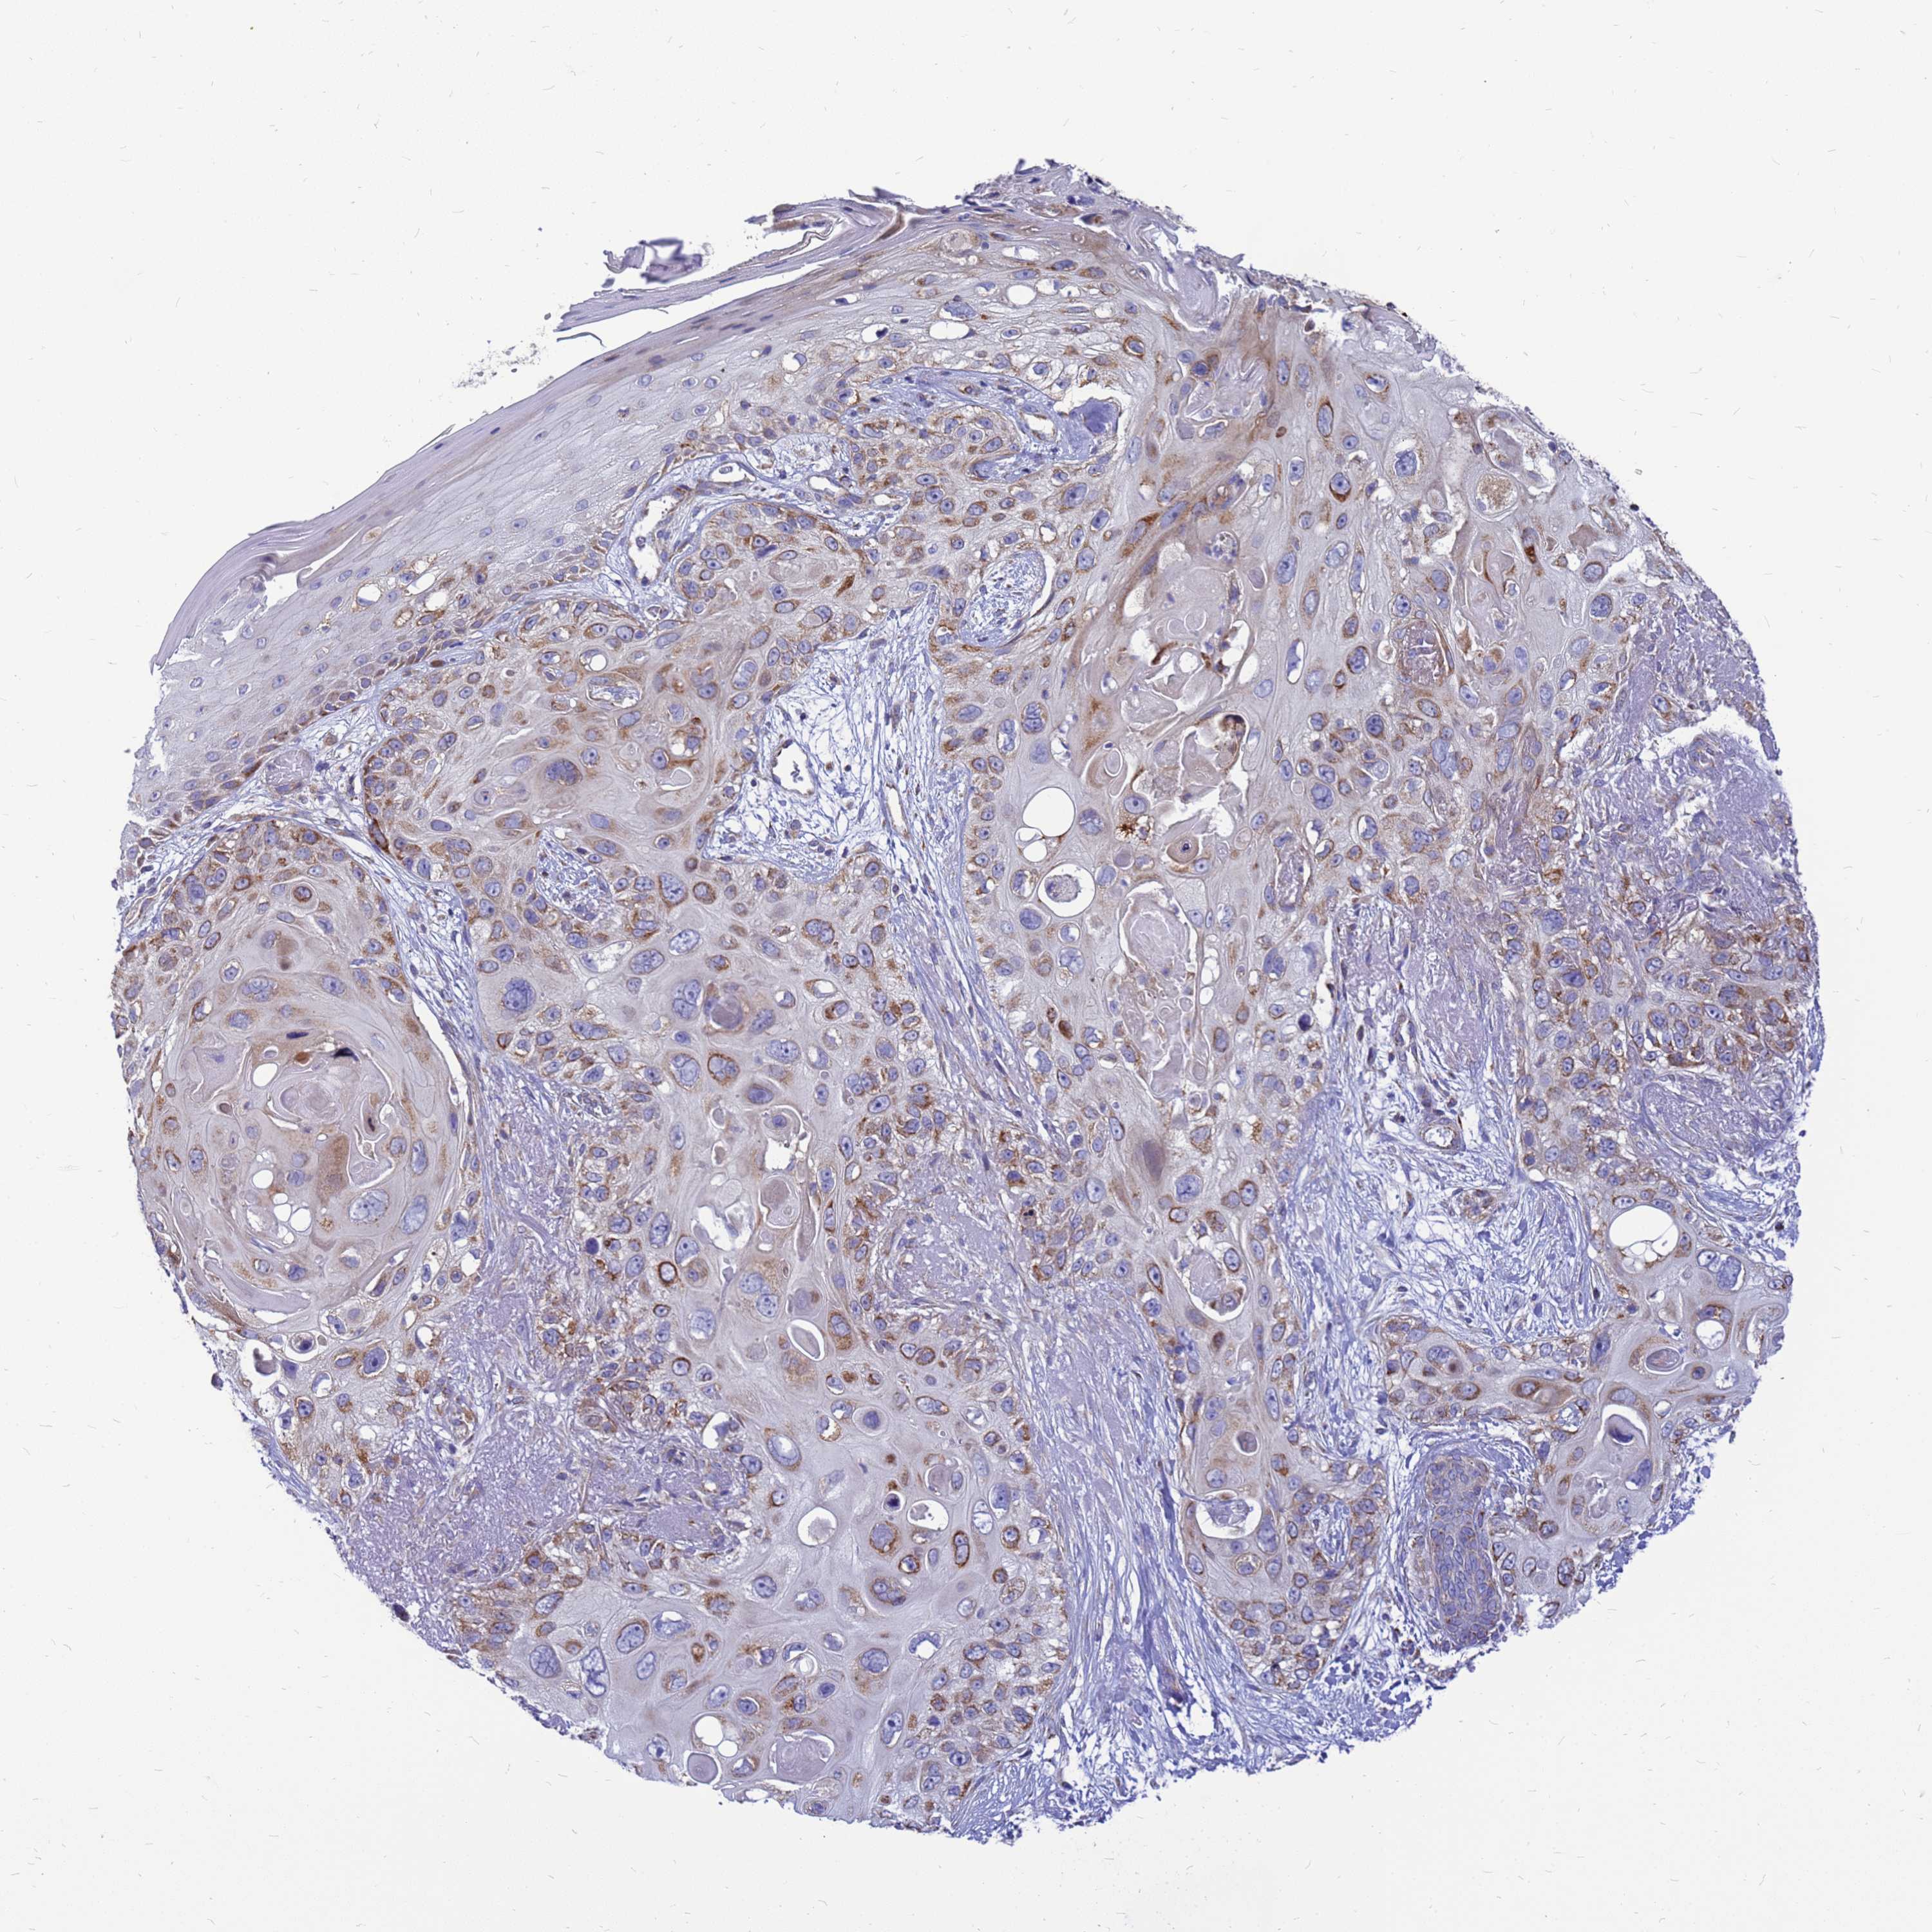

Basal cell and squamous cell cancer

SKIN CANCER - Protein expressioni

A mouse-over function shows sample information and annotation data. Click on an image to view it in a full screen mode. Samples can be filtered based on level of antibody staining by selecting one or several of the following categories: high, medium, low and not detected. The assay and annotation is described here.

Antibody stainingi

Antibody staining in the annotated cell types in the current human tissue is reported as not detected, low, medium, or high, based on conventional immunohistochemistry profiling in selected tissues. This score is based on the combination of the staining intensity and fraction of stained cells.

Each image is clickable and will lead to virtual microscopy that enables deeper exploration of all samples and also displays staining intensity scores, fraction scores and subcellular localization as well as patient and tissue information for each sample.

Antibody HPA045866

Staining

High

Medium

Low

Not detected

Intensity

Strong

Moderate

Weak

Negative

Quantity

>75%

75%-25%

<25%

None

Location

Nuclear

Cytoplasmic/membranous

Cytoplasmic/membranous,nuclear

Squamous cell carcinoma, metastatic, NOS

Squamous cell carcinoma, NOS